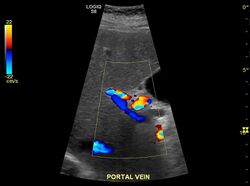

Hepatofugal (non-forward) flow in portal vein

Imaging

Ultrasound is routinely used in the evaluation of cirrhosis.[36] It may show a small and shrunken liver in advanced disease. On ultrasound, there is increased echogenicity with irregular appearing areas.[54] Other suggestive findings are an enlarged caudate lobe, widening of the fissures and enlargement of the spleen.[55] An enlarged spleen, which normally measures less than 11–12 cm in adults, may suggest underlying portal hypertension.[56] Ultrasound may also screen for hepatocellular carcinoma and portal hypertension.[36] This is done by assessing flow in the hepatic vein.[57] An increased portal vein pulsatility may be seen. However, this may be a sign of elevated right atrial pressure.[58] Portal vein pulsatility are usually measured by a pulsatility indices (PI).[57] A number above a certain values indicates cirrhosis (see table below).